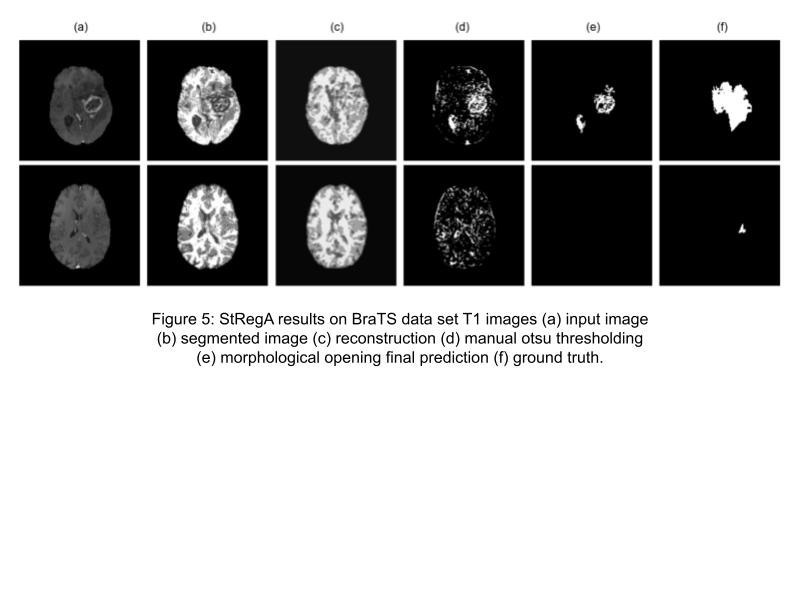

Figure 5: StRegA results on BraTS data set T1 images (a) input image (b) seg- mented image (c) reconstruction (d) manual otsu thresholding (e) morphological opening final prediction (f) ground truth.

DICE was used to evaluate both the T1 and T2 models. It can be seen in table 2 and 3 that StRegA outperformed its counterparts. The table also shows that the T2 model performs better than the T1 model. After all, this might be intuitive since tumors are more visible in T2 images. In figures 5 and 6, under-sampling is visible in every sample when comparing column (e) with the ground truth in (f). Once again, the T2 model performs better here with their final outcome being closer to the ground truth than the T1 model even though under-sampling is present. It is worth mentioning that the T1 model was trained with regular T1 images but tested with T1 contrast enhanced images, it is unknown how this affected the performance of the model if at all. What was noticeable about the performance of the model was that subtle anomalies were not detected, this can be seen in the second row of figure 5. That subtle anomaly was in a T1 image, it is unknown if the T2 model would have recognized an anomaly of similar size. If it does, then maybe the T2 model should be standard. Overall, reconstructing subtle anomalies with an acceptable error rate (labeling it as normal) is a shortcoming of reconstruction methods, especially with VAE approaches.